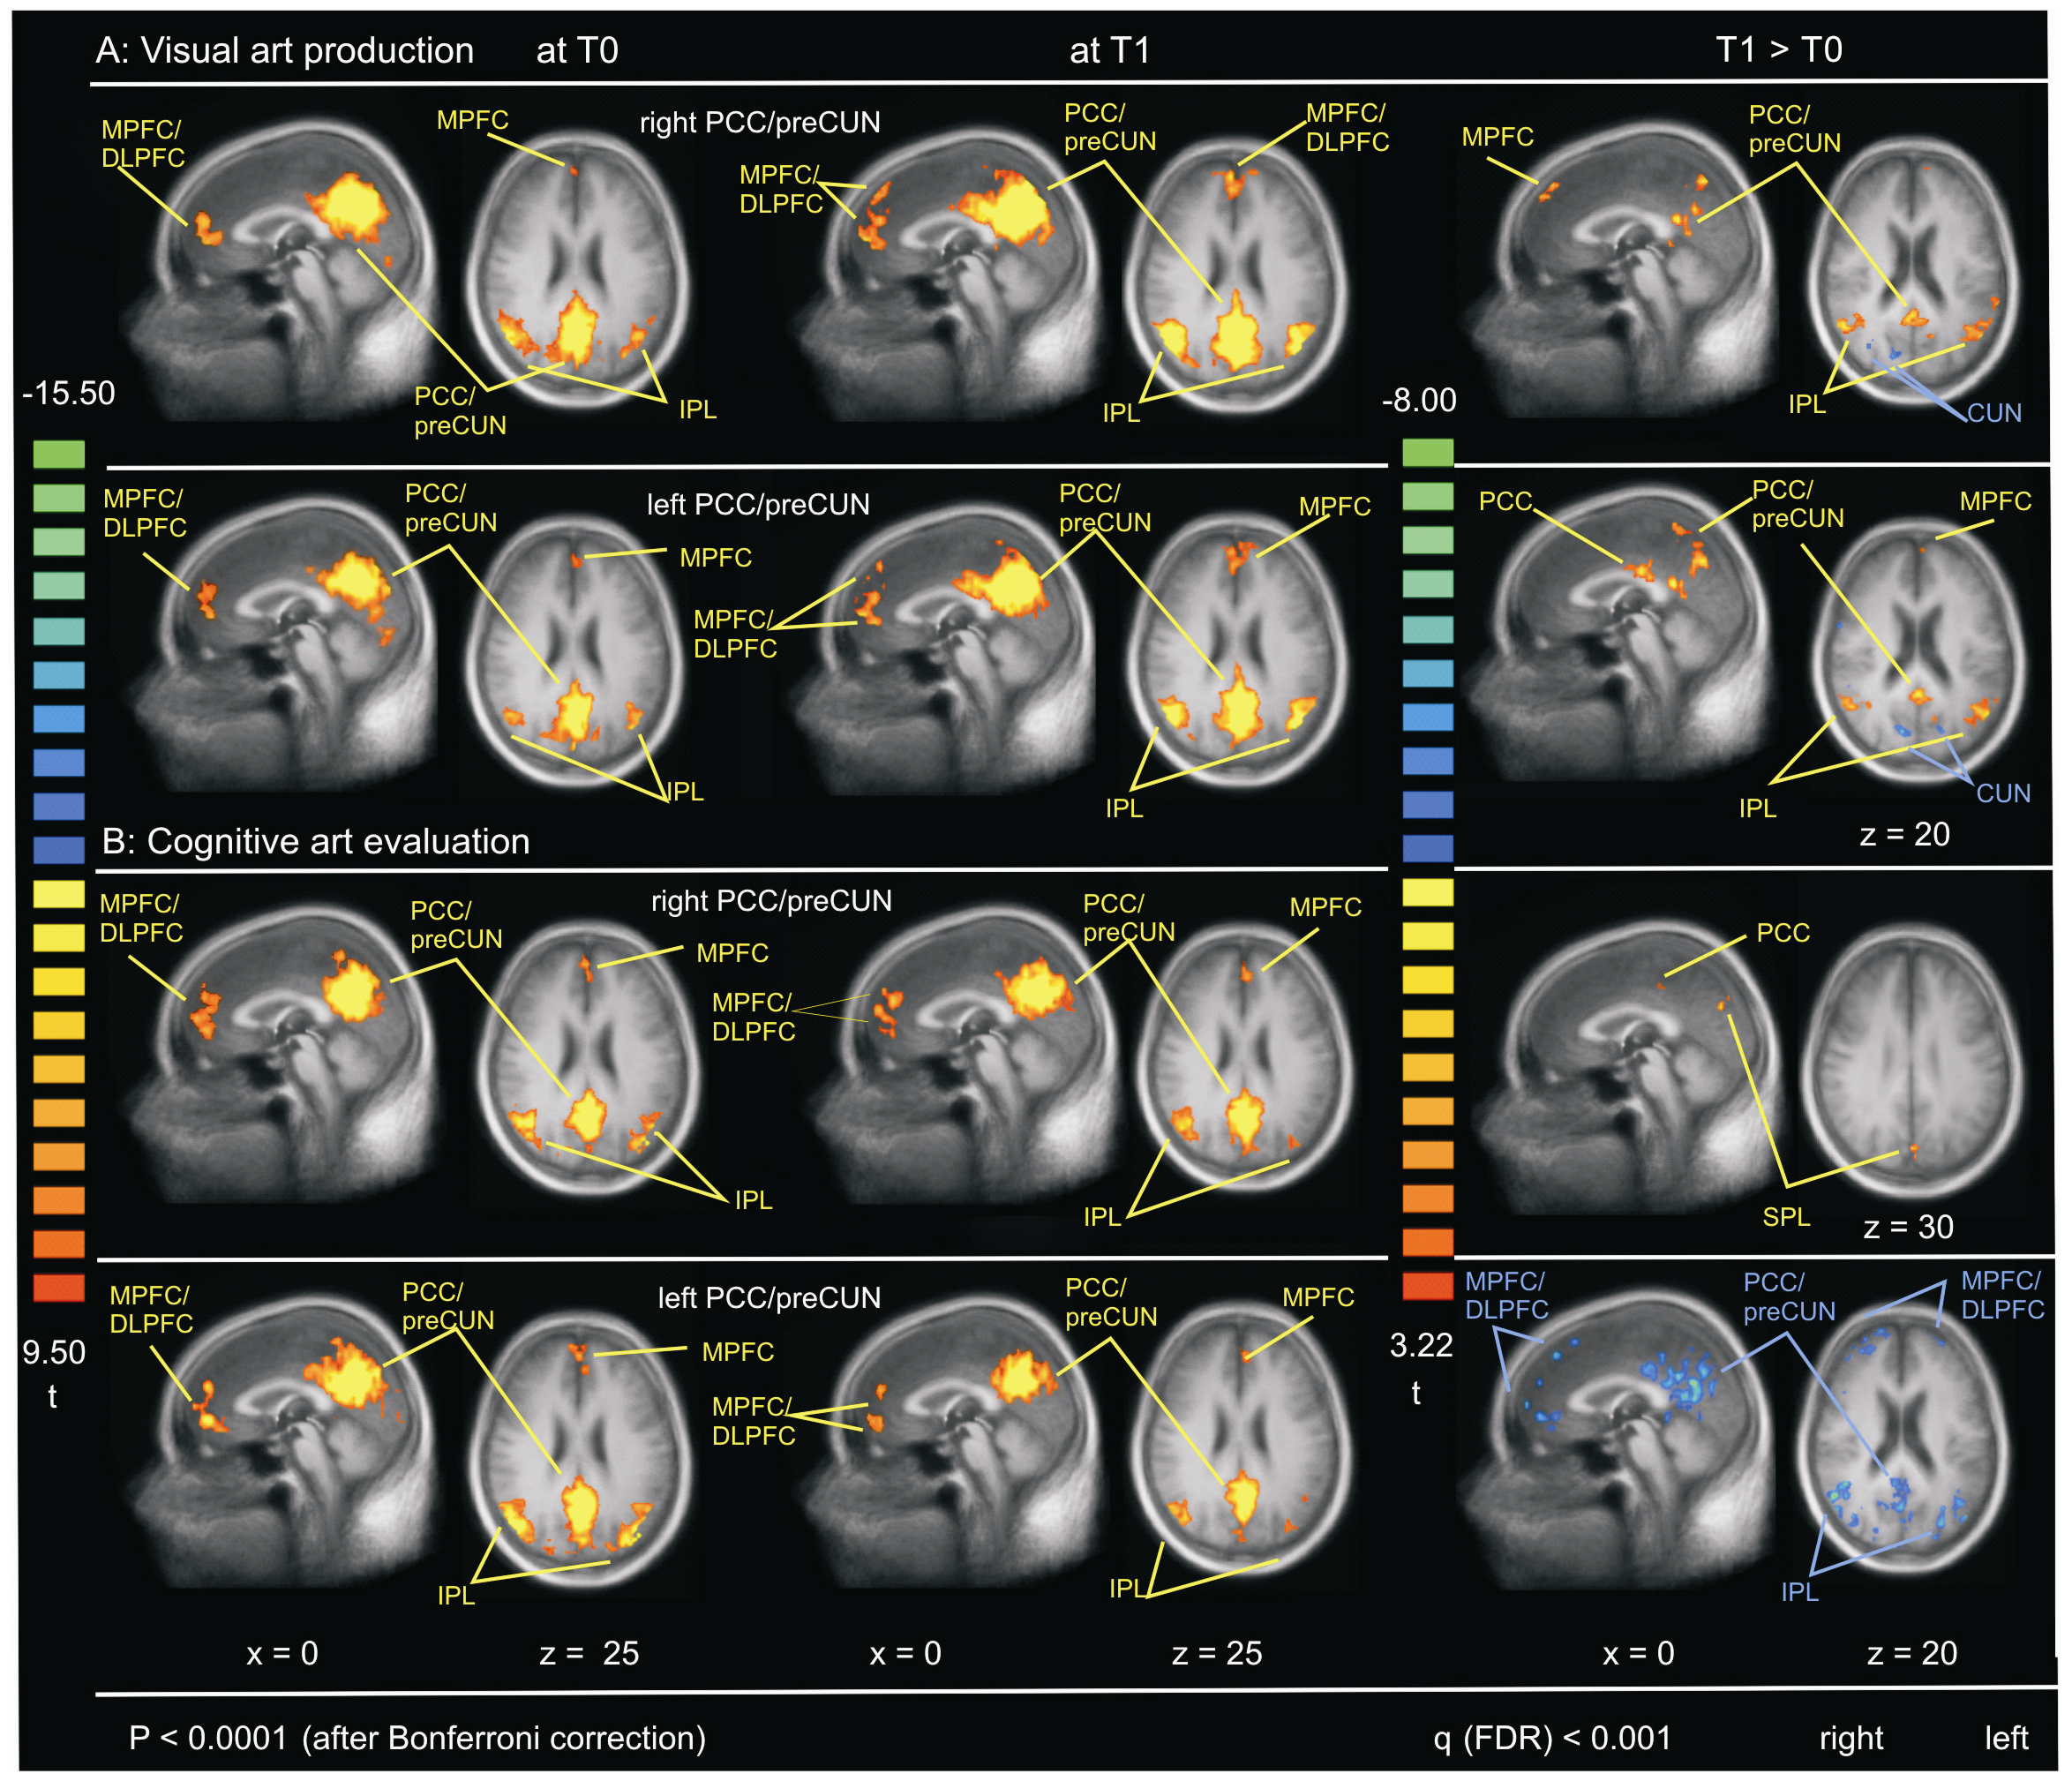

La seconde séance d’IMRf montra une amélioration de la connectivité de certaines régions cérébrales en RMD, notamment dans la région du cortex cingulaire postérieure droite, région impliqué ,entre autres, dans la mémoire autobiographique (la mémoire multimodale des évènements de sa propre vie) et le cortex préfrontal, impliqué dans la conscience de soi.

IRMf du groupe A, de production picturale et B d’analyse artistique. Avec T0 avant le stage, T1 après le stage et T1>T0 différence d’activité entre les deux mesures.